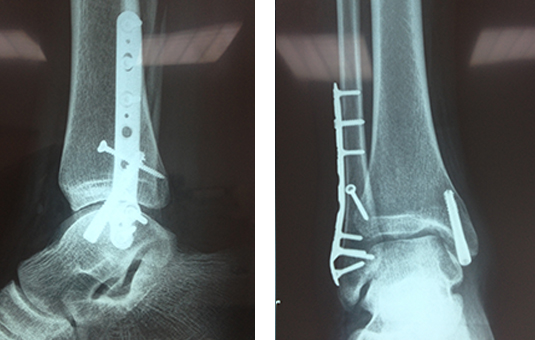

CORRECCIÓN DE AFLOJAMIENTO DE PRÓTESIS 1.PRÓTESIS AFLOJAMIENTO E INFECCIÓN DE VARIOS AÑOS. 2. RETIRO DE LA PRÓTESIS Y COLOCACIÓN DE PERLAS DE ANTIBIÓTICO ENTREVISTA PROGRAMA VIDA ENTREVISTA BDP CANAL 5 ENTREVISTA PIE PLANO ENTREVISTA ZAPATOS CORRECTOS INFILTRACIÓN DE ÁCIDO HYALURONICO EN CADERA